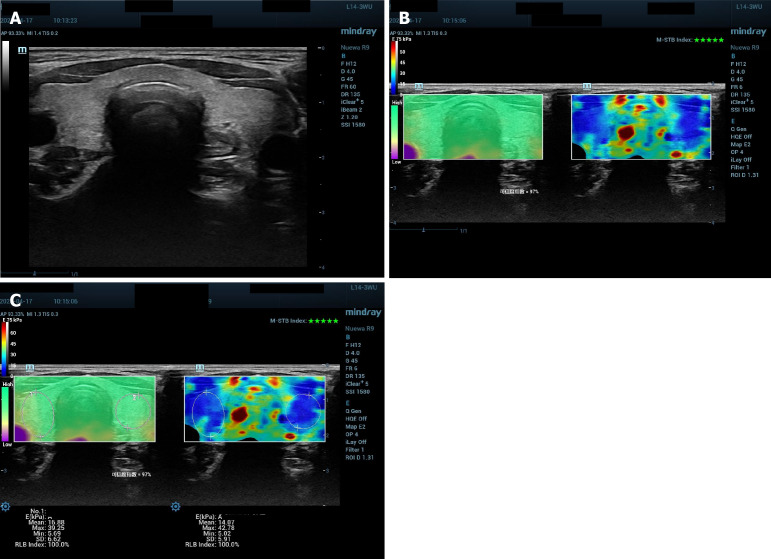

Methods: We included outpatients of reproductive age in the Department of Gynecology in Shanghai Changning Maternity and Infant Health Hospital between March 2023 and March 2024 who had conventional ultrasound examination and 2D SWE of the thyroid. They also underwent transvaginal ultrasound examination to confirm early intrauterine pregnancy and serum thyroid stimulating hormone (TSH) level was measured. The patients were divided into pregnant with normal TSH, pregnant with abnormal TSH, and nonpregnant with normal TSH. Conventional ultrasound and 2D SWE results were compared among the three groups.

Results: A total of 108 patients were included in the study; 57 in the pregnant with normal TSH group, 18 in the pregnant with abnormal TSH group and 33 were in the nonpregnant with normal TSH group. Thyroid size, thyroid echotexture, 2D SWE quantitative parameters including mean elasticity in the region of interest and maximal elasticity in the region of interest showed no significant differences among the three groups (P > 0.05).

Conclusion: Conventional ultrasound and 2D SWE features could not reflect the level of serum TSH.